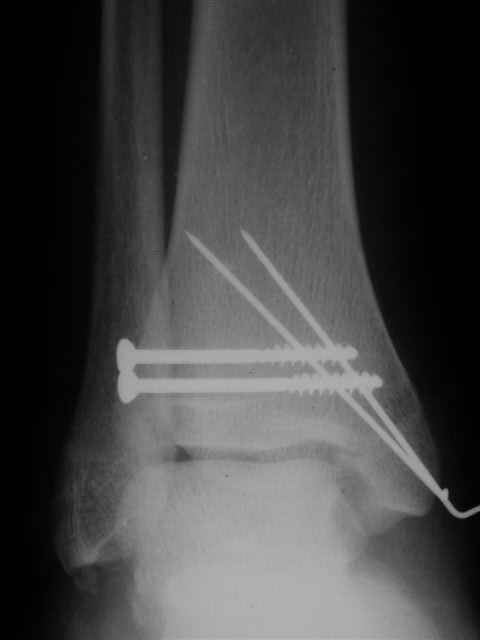

Я предупреждал, что ничего сверхъестественного. Каюсь, что одна из спиц прошла несколько дальше, чем нужно было, но главное - перелом стабилизирован и больной работает суставом в полном объёме, несмотря на представленную раннее травму коленного сустава.